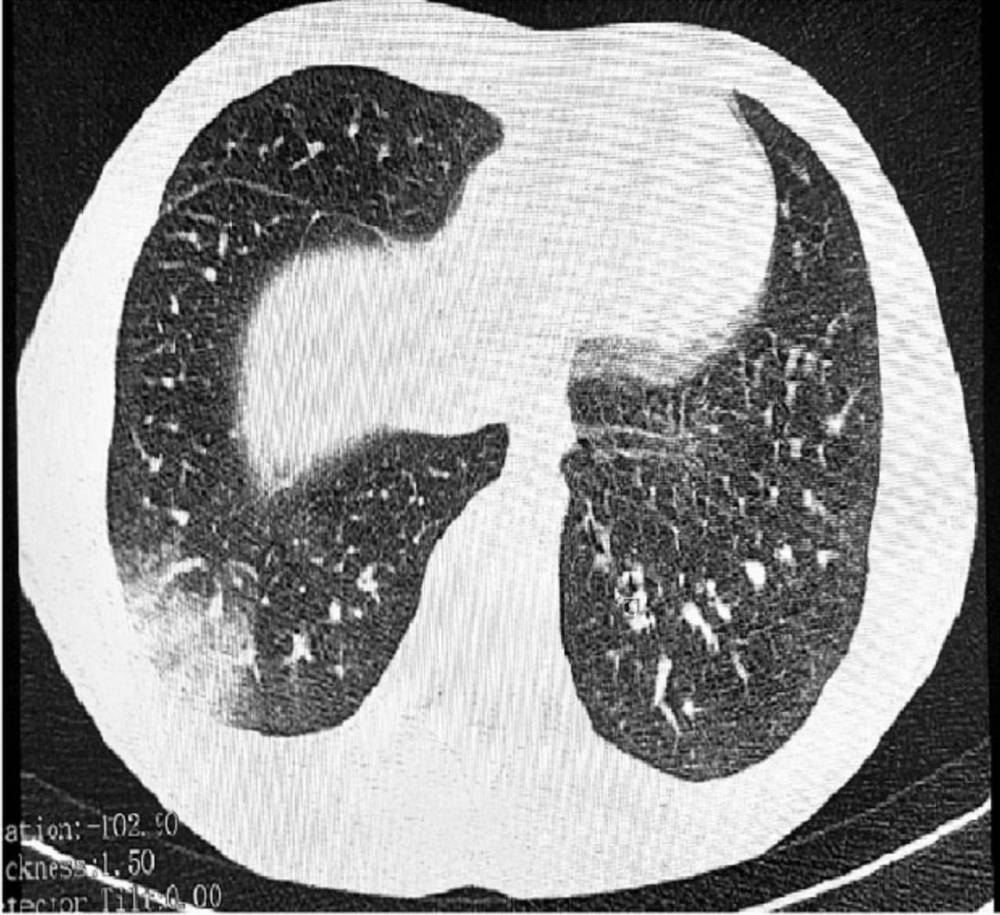

ووفقًا لتقرير صادر عن هيئة حماية حقوق المستهلك الروسية «روسبوتريبنادزور»، تم تشخيص المراهق، الذي لم يُكشف عن هويته، بمرض EVALI بعد معاناته من أعراض تنفسية حادة، شملت ضيقًا في التنفس، وسعالًا مستمرًا وآلامًا في الصدر، وبعد الفحوصات الطبية تبين أن الإصابة مرتبطة مباشرة باستخدامه المنتظم للسجائر الإلكترونية «الفيب» وخصوصا تلك التي تحتوي على نكهات متنوعة. وأشار الأطباء إلى أن حالته تشمل التهاب القصيبات المسدة، وهي حالة رئوية خطيرة قد تؤدي إلى ضرر دائم في الرئتين.

وتم نقل المراهق إلى أحد مستشفيات تومسك لتلقي العلاج، حيث يخضع حاليًا للرعاية الطبية المكثفة، في حين أكدت التقارير أن الشاب كان من المدخنين الشرهين للسجائر الإلكترونية، مما يسلط الضوء على المخاطر المحتملة للاستخدام المفرط لهذه المنتجات.

من جانبها، أشارت السلطات الطبية في تومسك إلى أنها تعمل على تحليل المواد المستخدمة في السجائر الإلكترونية التي استخدمها المراهق، لتحديد ما إذا كانت تحتوي على مواد كيميائية ضارة مثل أسيتات الفيتامين E، التي رُبطت بحالات EVALI في دول أخرى.